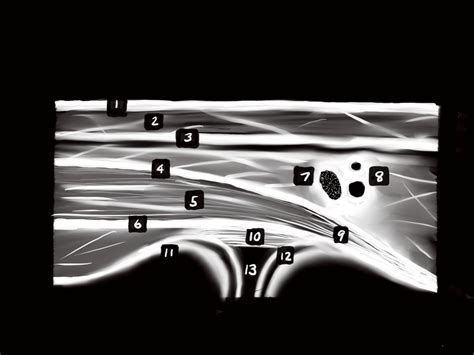

At its core, Musculoskeletal Ultrasound relies on the pulse-echo principle. A transducer probe emits sound waves that penetrate the skin and reflect off various tissues. These echoes are then converted into detailed, grayscale images on a screen. Because different tissues have varying densities, they appear differently on the ultrasound display—a concept known as echogenicity.